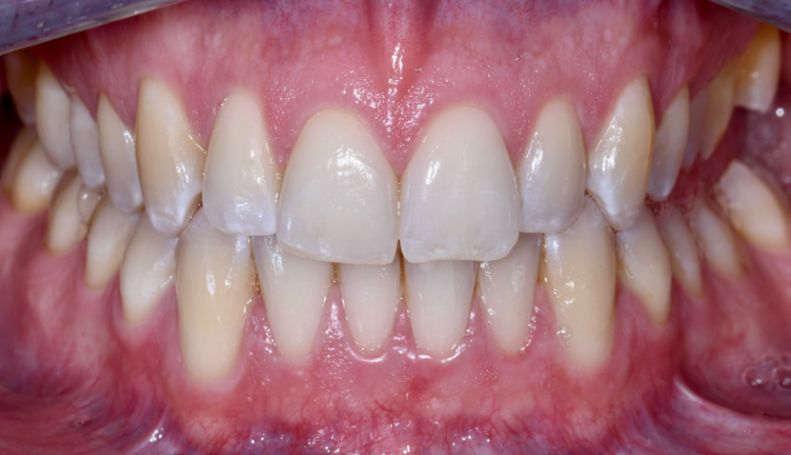

Restorative treatment of a persistent, unilateral open bite with direct composite table tops

Reconstructions of posterior teeth that extend over multiple cusps or even the entire occlusal surface are typically performed…